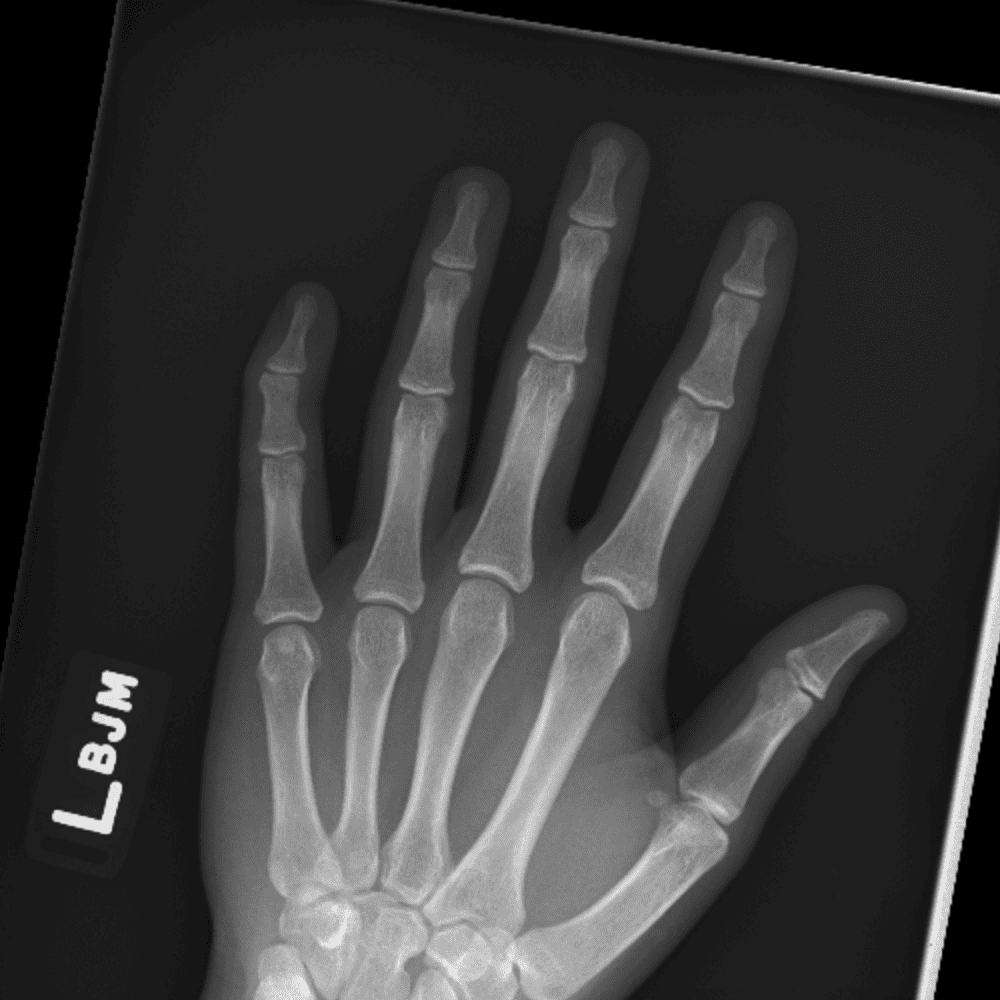

Simulates call by including subtle or difficult cases and some normals.

30 cases